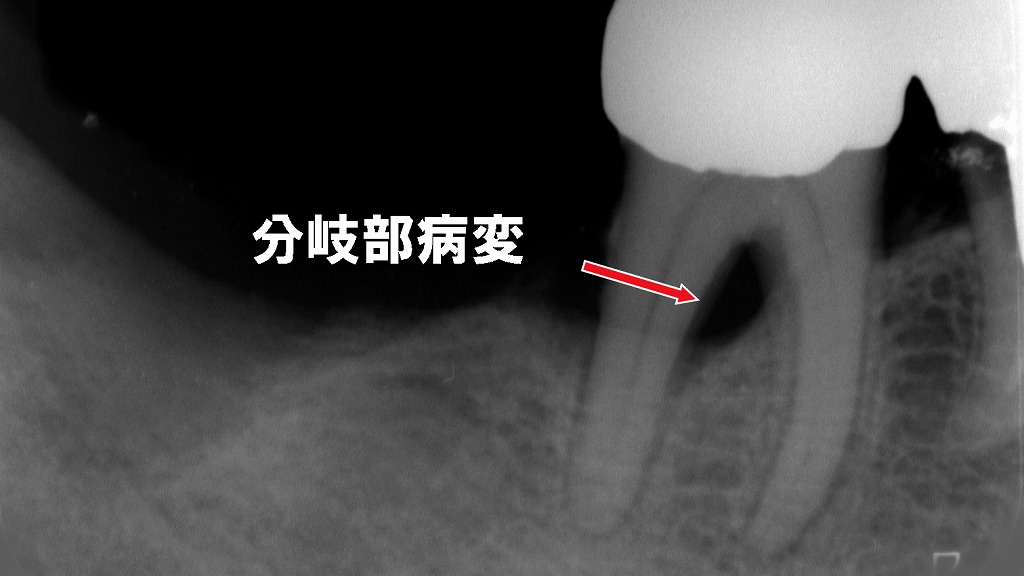

🖼️ 同症例のレントゲン写真での確認

- レントゲン上で第2小臼歯から第1大臼歯にかけて骨の著しい吸収を確認

- 骨が溶けた部分は黒く写る

- 第2小臼歯では歯根膜腔の拡大も認められ、動揺度は2度(横に1〜2mm動く)

- 大臼歯の根分岐部(分岐部病変)には湾曲したプローブを使用する

赤矢印部は大臼歯の分岐部に認められる骨吸収。分岐部病変の診断には、部位・深さ・方向性を正確に把握できるプローブの選択が重要です。

通常のポケット計測には真っ直ぐなプローブ、分岐部の評価には湾曲したプローブを使用し、根分岐への進入度を立体的に確認します。